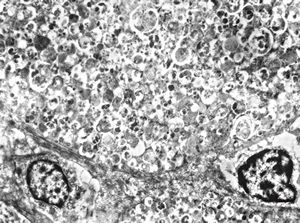

normal seromucinous salivary gland